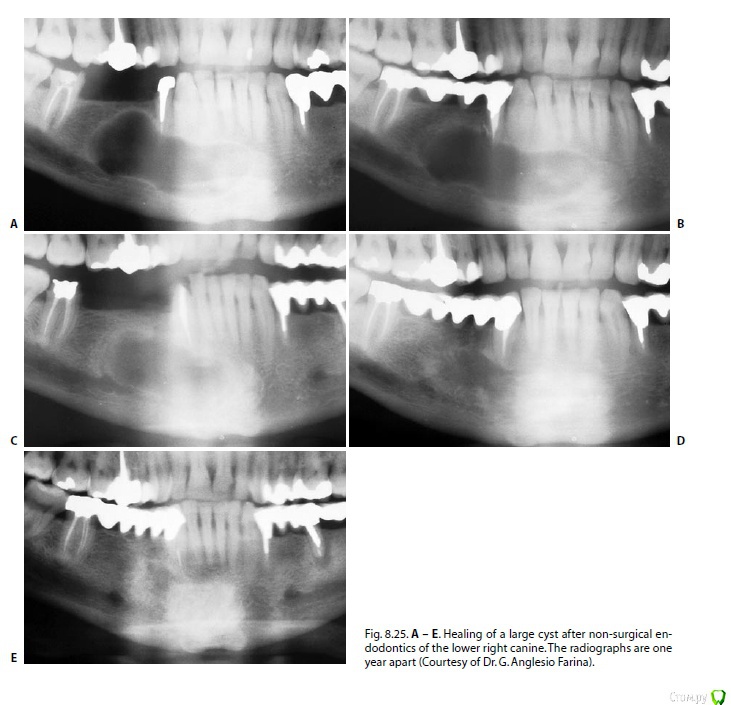

Fred Опубликовано 2 марта, 2017 Поделиться Опубликовано 2 марта, 2017 Я до сих пор толком не разбираюсь в "кистологии". Давайте и на этом форуме побеседуем. Теоретический вопрос - исчезнет ли киста в 100% случаев, если СКК стерилизировать и стерильность ее поддерживать на продолжительном отрезке времени? "Давайте обновим знания в "кистологии".Обратилась ко мне пациента по почте с кистоподобным образованием в области верхней челюсти, у передних зубов (прилагаю ее снимки в первой картинке: первый снимок - полгода назад, другие - на днях). Недавняя моя неудача с много раз презентированным на форумах случаях с кистообразным поражением заставило меня посидеть с литературой и еще раз понять, что же такое происходит во время таких поражений, и что мешает возникнуть заживлению Пациентка утверждала, что канал ей пломбировали года 3 назад, но теперь снова возникла симптоматика и опухание. Рядомстоящие витальные, но резец уже депульпировали, так как собираются кисту вырезать.Я еще раз хочу разобраться, если киста стерильна, то почему возникает симптоматика? Может симптоматику в таких случаях поддерживает то, что мы не можем идеально запломбировать канал, и несмотря на красивую рнг-картинку, мы имеем некачественную обтурацию в апексе, которая и поддерживает временно обостряющуюся клинику? Может образованию не дает возможность исчезнуть то, что это пузырь с жидкостью, хоть и стерильный, и в нем не могут возникнуть репарационные процессы, так как в нем нет кровотока? Может нужно все-таки его насильно сдувать, сплющивать, вырезать? Вчера прочитал раздел Кастеллучи про периапикальные поражения (обновил знания, давно за стоматологическими книгами не сидел), и понял, что все это лечится либо банальной эндодонтией, либо ретроградкой, если эндо не получилось. Никаких специальных хирургических методов, никаких вырезаний, никаких жертв витальности соседних зубов.Так нужен ли специальный подход к "кистам"?Побеседуем?Кто захочет тоже почитать Кастеллучи, но не имеет, просите, дам ссылку или перешлю." 3 Ссылка на комментарий

Dok22 Опубликовано 4 марта, 2017 Поделиться Опубликовано 4 марта, 2017 (изменено) Часто путают два состояния киста и периапикальный абсцесс с полостью. Так как на снимках они выглядят одинаково. Одонтогеные кисты например фолликулярные и радикулярные появляются по причине раздражения эпителия(островки Маляссе) начинается их "рост" и увеличиваются они за счет давления жидкости которую продуцирует эпителий в кисту.Течение без симптомное,обнаруживаем случайно(КТ) или в случае обострения при ее инфицировании. Лечится декомпрессией очага.Само по себе состояние киста редкое. Изменено 4 марта, 2017 пользователем Dok22 Ссылка на комментарий

Dok22 Опубликовано 4 марта, 2017 Поделиться Опубликовано 4 марта, 2017 Периапикальный абсцесс возникает по причине периодических выбросов флоры из недопломбированного канала в периапикальные ткани происходит разрушение кости и образование гранулемы. В отличии от кисты симптоматика практически всегда есть.Еще как правило есть свищевой ход который может открываться в том числе и в нос и пазухи(гайморит). Лечится предотвращением попадания флоры в очаг,если это условие выполнено полость гарантированно заживет. Ссылка на комментарий